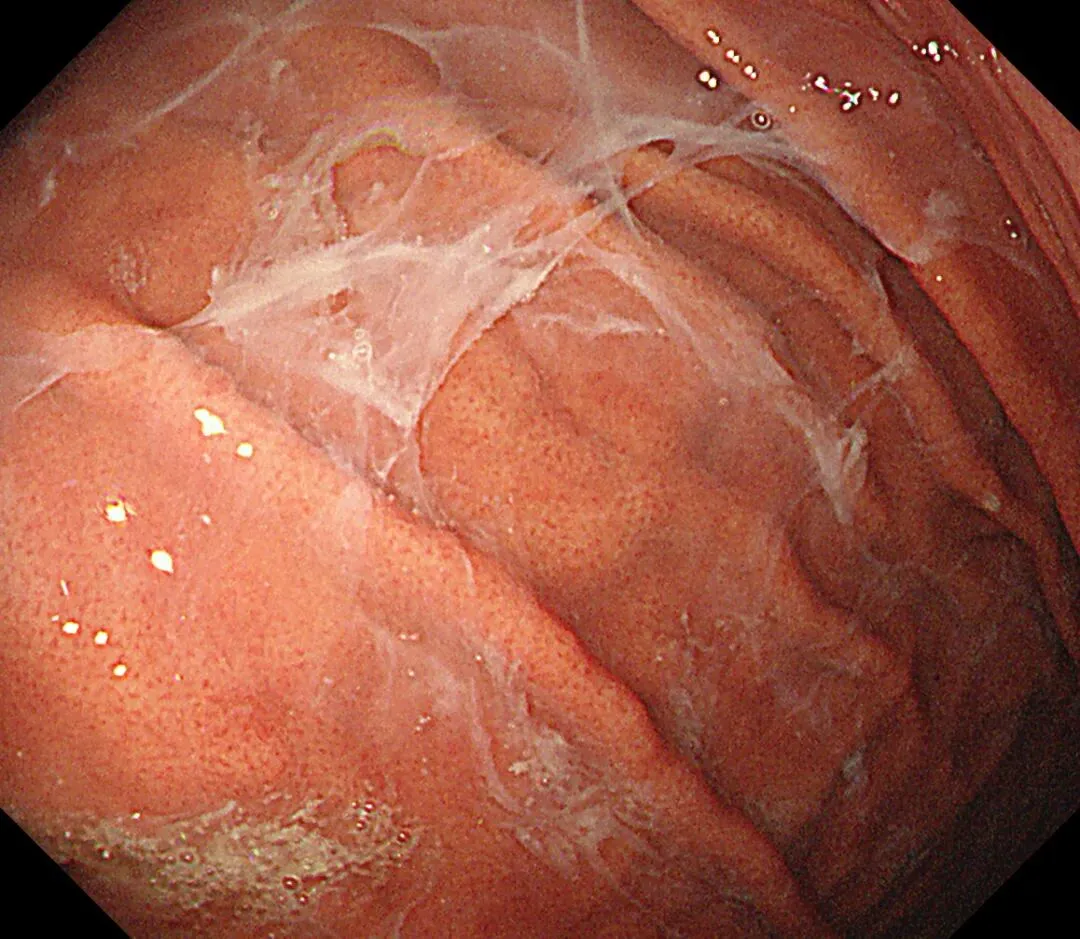

蛛网状黏液case3,服用P-CAB药物(具体服用时长不详)👇